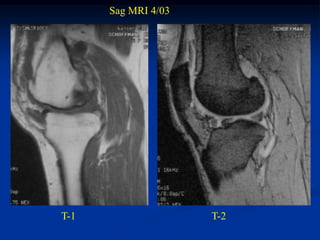

Case #1170.1              P.O. desmoid

61 year female with OA knee in 3/06 prior to TKA

Sag MRI 4/03

T-1                  T-2

MRI 1 year PO TKA

Sag T-2                       Gad

Axial

Gad